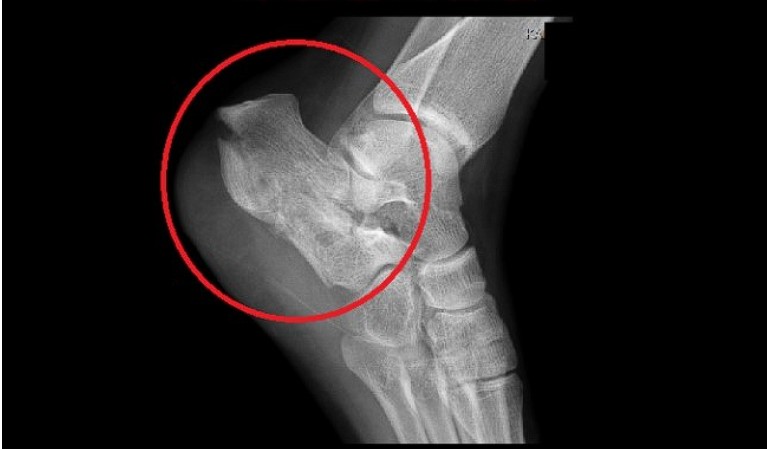

초기에는 밤에만 불편함을 느끼다가 점점 지속 시간도 늘어납니다.3. 족저근막염

발바닥 통증의 대표 질환으로,

발뒤꿈치에서 발바닥 전체로 이어지는 근막에 염증이 생기며

걷거나 서 있을 때 발바닥이 뜨겁고 찌릿한 통증을 유발합니다.

특히 아침에 첫 발을 디딜 때 더 아픈 경우가 많아요.